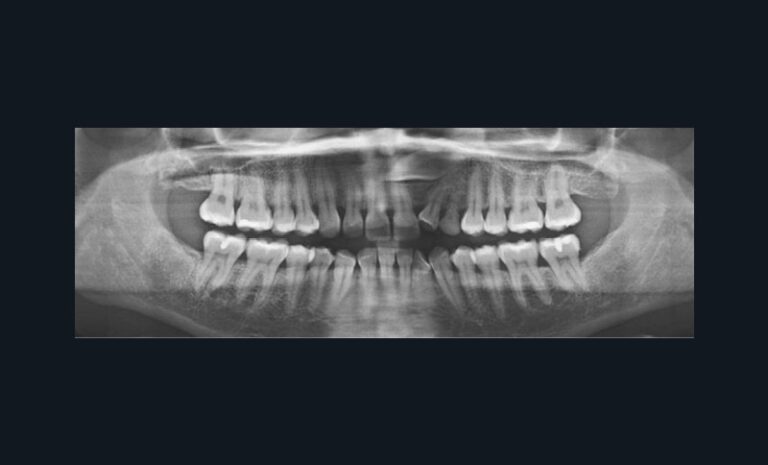

L’illusion du mouvement est illustrée dans l’exemple clinique (fig. 4) qui montre une ingression molaire pure sans effet sur les dents d’ancrage.

Cet exemple est caricatural et son absurdité semble évidente, mais une torsion de la réalité clinique existe plus ou moins à chaque étape de la simulation, pour chaque aligneur. Et les imprécisions s’accumulent avec le nombre d’aligneurs contribuant ainsi à la difficulté de voir la prédiction virtuelle devenir réalité : en moyenne, les mouvements s’expriment à 50 % de leur planification [1-3].